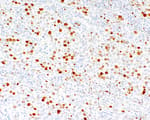

Mouse anti-Estrogen Receptor Alpha Monoclonal Antibody [119-13]

Bethyl Laboratories Catalog # A500-026A A500-026A-T

ValidatedDocuments (8)Mouse anti-Estrogen Receptor Alpha Monoclonal Antibody [119-13]

Validation Performed

All Bethyl Laboratories® antibodies are validated to meet our strict performance standards.

Target: Estrogen Receptor Alpha

Reactivity: Human

Applications:

Host: Mouse

Clonality: Monoclonal

Conjugate:

Purity:

For ordering information, see our International Distributors

Product has been discontinued